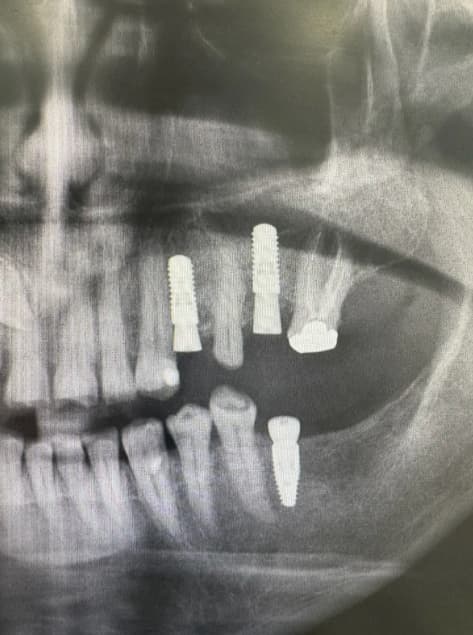

Dental implants are small titanium posts that are carefully placed into the jawbone to serve as replacements for the roots of missing teeth. These implants provide a secure and durable foundation for artificial teeth such as crowns, bridges, or dentures. At Smile Point Dental, we utilize advanced methods and personalized care to ensure your dental implants are functional, long-lasting, and look completely natural.

Dr. Ardeshir Ranjbari brings a wealth of clinical knowledge and international training to every dental implant case at Smile Point Dental. Having practiced in both Tehran and Aachen, he developed a deep understanding of complex restorative procedures and the importance of precise surgical planning. Dr. Ardeshir takes the time to assess your bone density, overall oral health, and long term goals before recommending the most suitable implant solution for your situation. Patients trust him for his calm, methodical approach and his ability to make even the most involved procedures feel manageable and stress free.